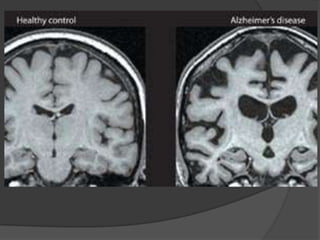

IMAGING IN DEMENTIA

ALZHEIMER’S DEMENTIA

Structural imaging



Cerebral atrophy (typical dilatation of lateral

ventricles & widening of cortical sulci) particularly in posterior temporal & parietal regions &

 specific brain regions like hippocampus and medial

temporal lobe.

Volumetric MRI reveals shrinkage in vulnerable

brain regions, particularly the medial temporal lobe

& Hippocampus.

Measurements of hippocampus is the most sensitive marker of

pathology of AD early in disease

Functional imaging

Early studies using PET or SPECT revealed a

characteristic pattern of hypometabolism in the posterior

parietal lobes.

MRS in AD revealed- Decreased conc of NAA in the

temporal lobes & increased conc of inositol in the

occipital lobes